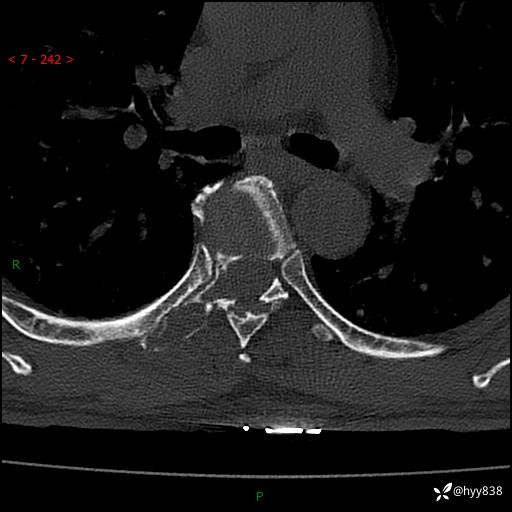

胸椎CT平扫(骨窗+软组织窗)